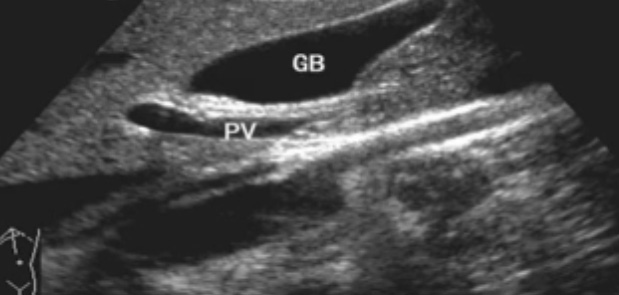

一、正常膽囊超聲圖像

膽囊的位置、形態、大小、壁厚,內部及附壁是否有異常回聲,尤其膽囊要注意頸部,還要看有沒慢性炎癥的征象,腫瘤或隆起樣病變.正常膽囊聲像圖是像個瓣,膽囊正常大小,頸部指向肝門膽囊輪廓清晰,壁薄很光滑呈線狀,囊內無回聲,后壁回聲增強。為什么無回聲呢?因為膽汁是液體,水,血液這些都是無回聲的。膽囊頸和門靜脈或門脈右支根部之間有一線狀高回聲帶連結,這是識別膽囊位置的重要標志。膽囊長徑一般不超90mm;前后徑2030mm,不超過40m正常充盈膽囊壁厚<3mm。 膽囊皺褶非常常見,

二、正常膽管超聲圖像

肝內膽管-無膽管擴張的情況下,超聲一般只能顯示膽管的一、二級支,不能顯示二級以上的肝內膽管肝外膽管(聲像圖上大致分為兩段)上段與門靜脈伴行,位于門靜脈主干的右前方;下段與下腔靜脈伴行并延伸進入胰頭背外側。膽道、肝動脈與門靜脈的關系。